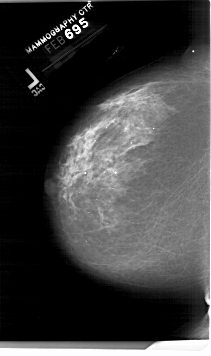

A_1999_1.RIGHT_CC

LEFT_CC LINES 6751 PIXELS_PER_LINE 4006 BITS_PER_PIXEL 12 RESOLUTION 43.5 NON_OVERLAY